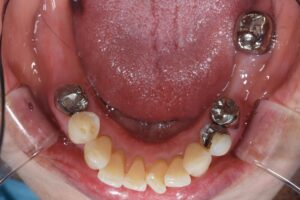

【インプラント埋入後】

画面向かって左下に2本のインプラントを埋入しました。処置時間は30分程度です。この患者様は術後、痛みやトラブルもなく、現在は治療終了しており、満足に食事ができるようになった、有難うございましたとのお言葉をかけて下さいました(*^-^*)

繰り返しになりますが、患者様は、現在入れ歯を使用しておりません。